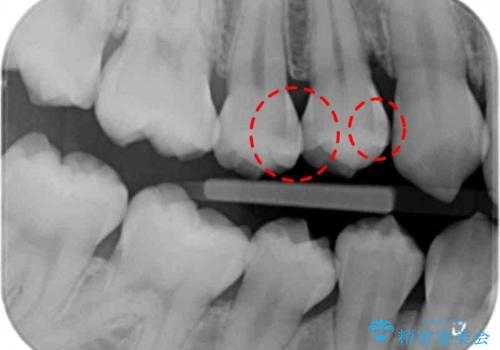

- 銀歯を白くしたいとのことで来院されました。

特に大きな虫歯もなかったため、周りの歯を残しつつセラミックインレーでの修復処置をしていきます。